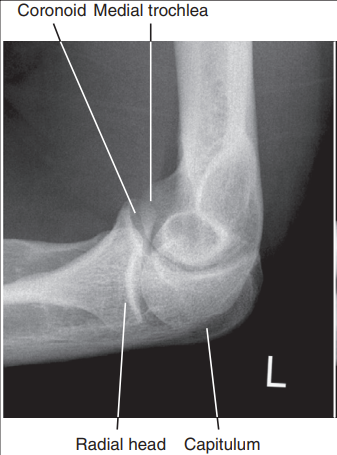

the distal capitulum surface is demonstrated too far distal to the distal surface of the medial trochlea and the radial head is placed too far posteriorly to the coronoid process

Proximal humerus is elevated

Distal capitulum is too far proximal to the distal medial trochlear surface of the radial head is too far anterior to the coronoid process

Distal forearm is depressed